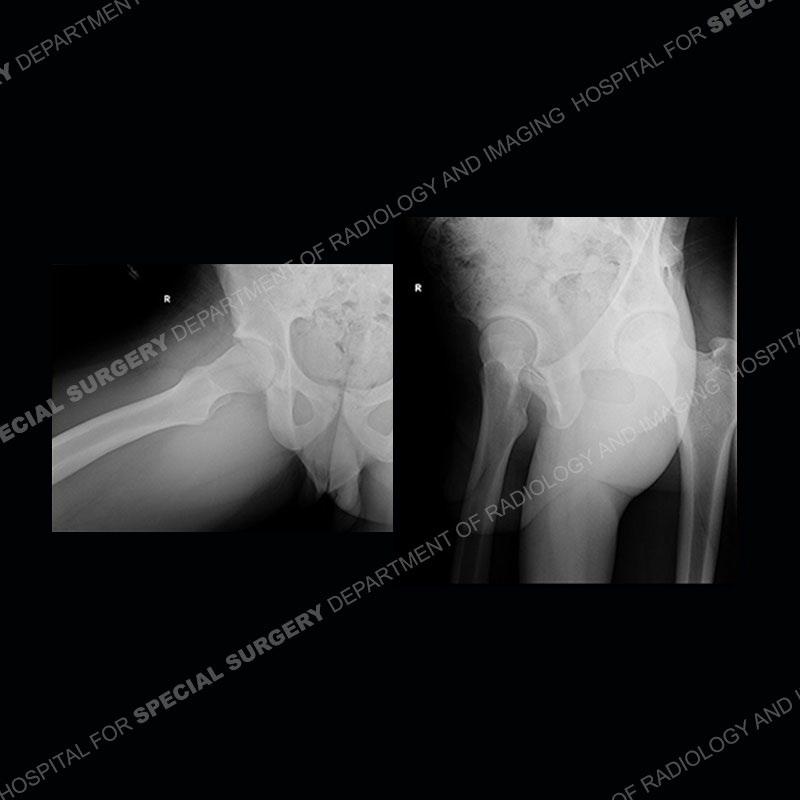

Radiographs did not demonstrate any clear abnormality. The MRI shows markedly abnormal signal of the right superior pubic ramus and abnormal signal/”mass” extending into the adjacent soft tissue. The inferior articular surface of the ramus showed what was thought to be bony destruction. CT examination shows a destructive process of the right superior pubic ramus.

This case was a bit surprising to all involved given that the young man is otherwise in good health and extremely active in sports. The original thought was this case was going to be an overuse injury or stress fracture. The pubic ramus with the adjacent physis acts as a metaphyseal equivalent and although not frequently thought of would be a reasonable location for infection/osteomyelitis. The first MRI was somewhat confusing as the process did not have an appearance of a stress injury or rectus adductor aponeurosis injury. The degree of edema of the bone and soft tissue together would be odd especially for a sports hernia process. Initially, the thought was of an aggressive process which could be infection or neoplastic. Particularly, the abnormal architecture of the inferior surface of the ramus looked like a destructive process.